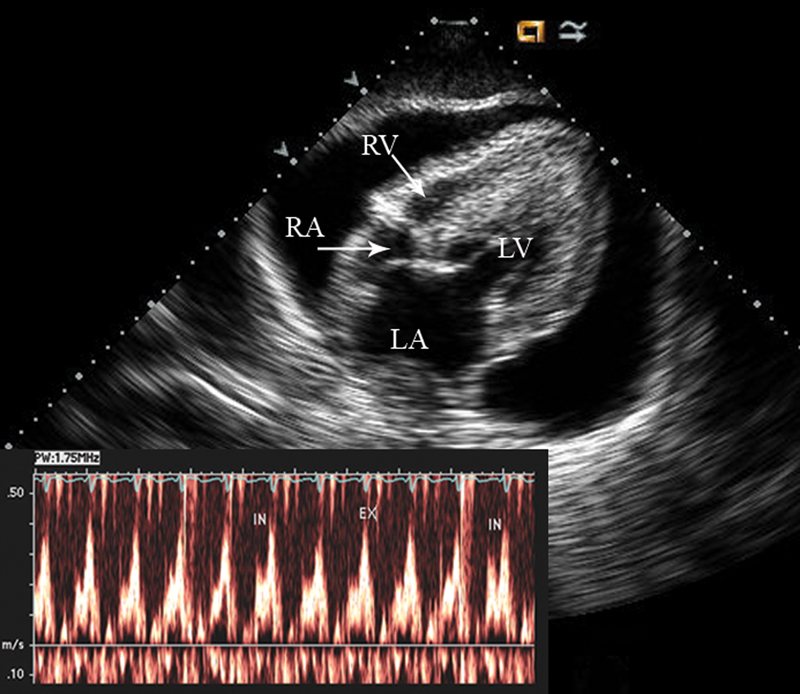

فحوصات تشخيصية لبعض امراض القلب والشرايين التاجية